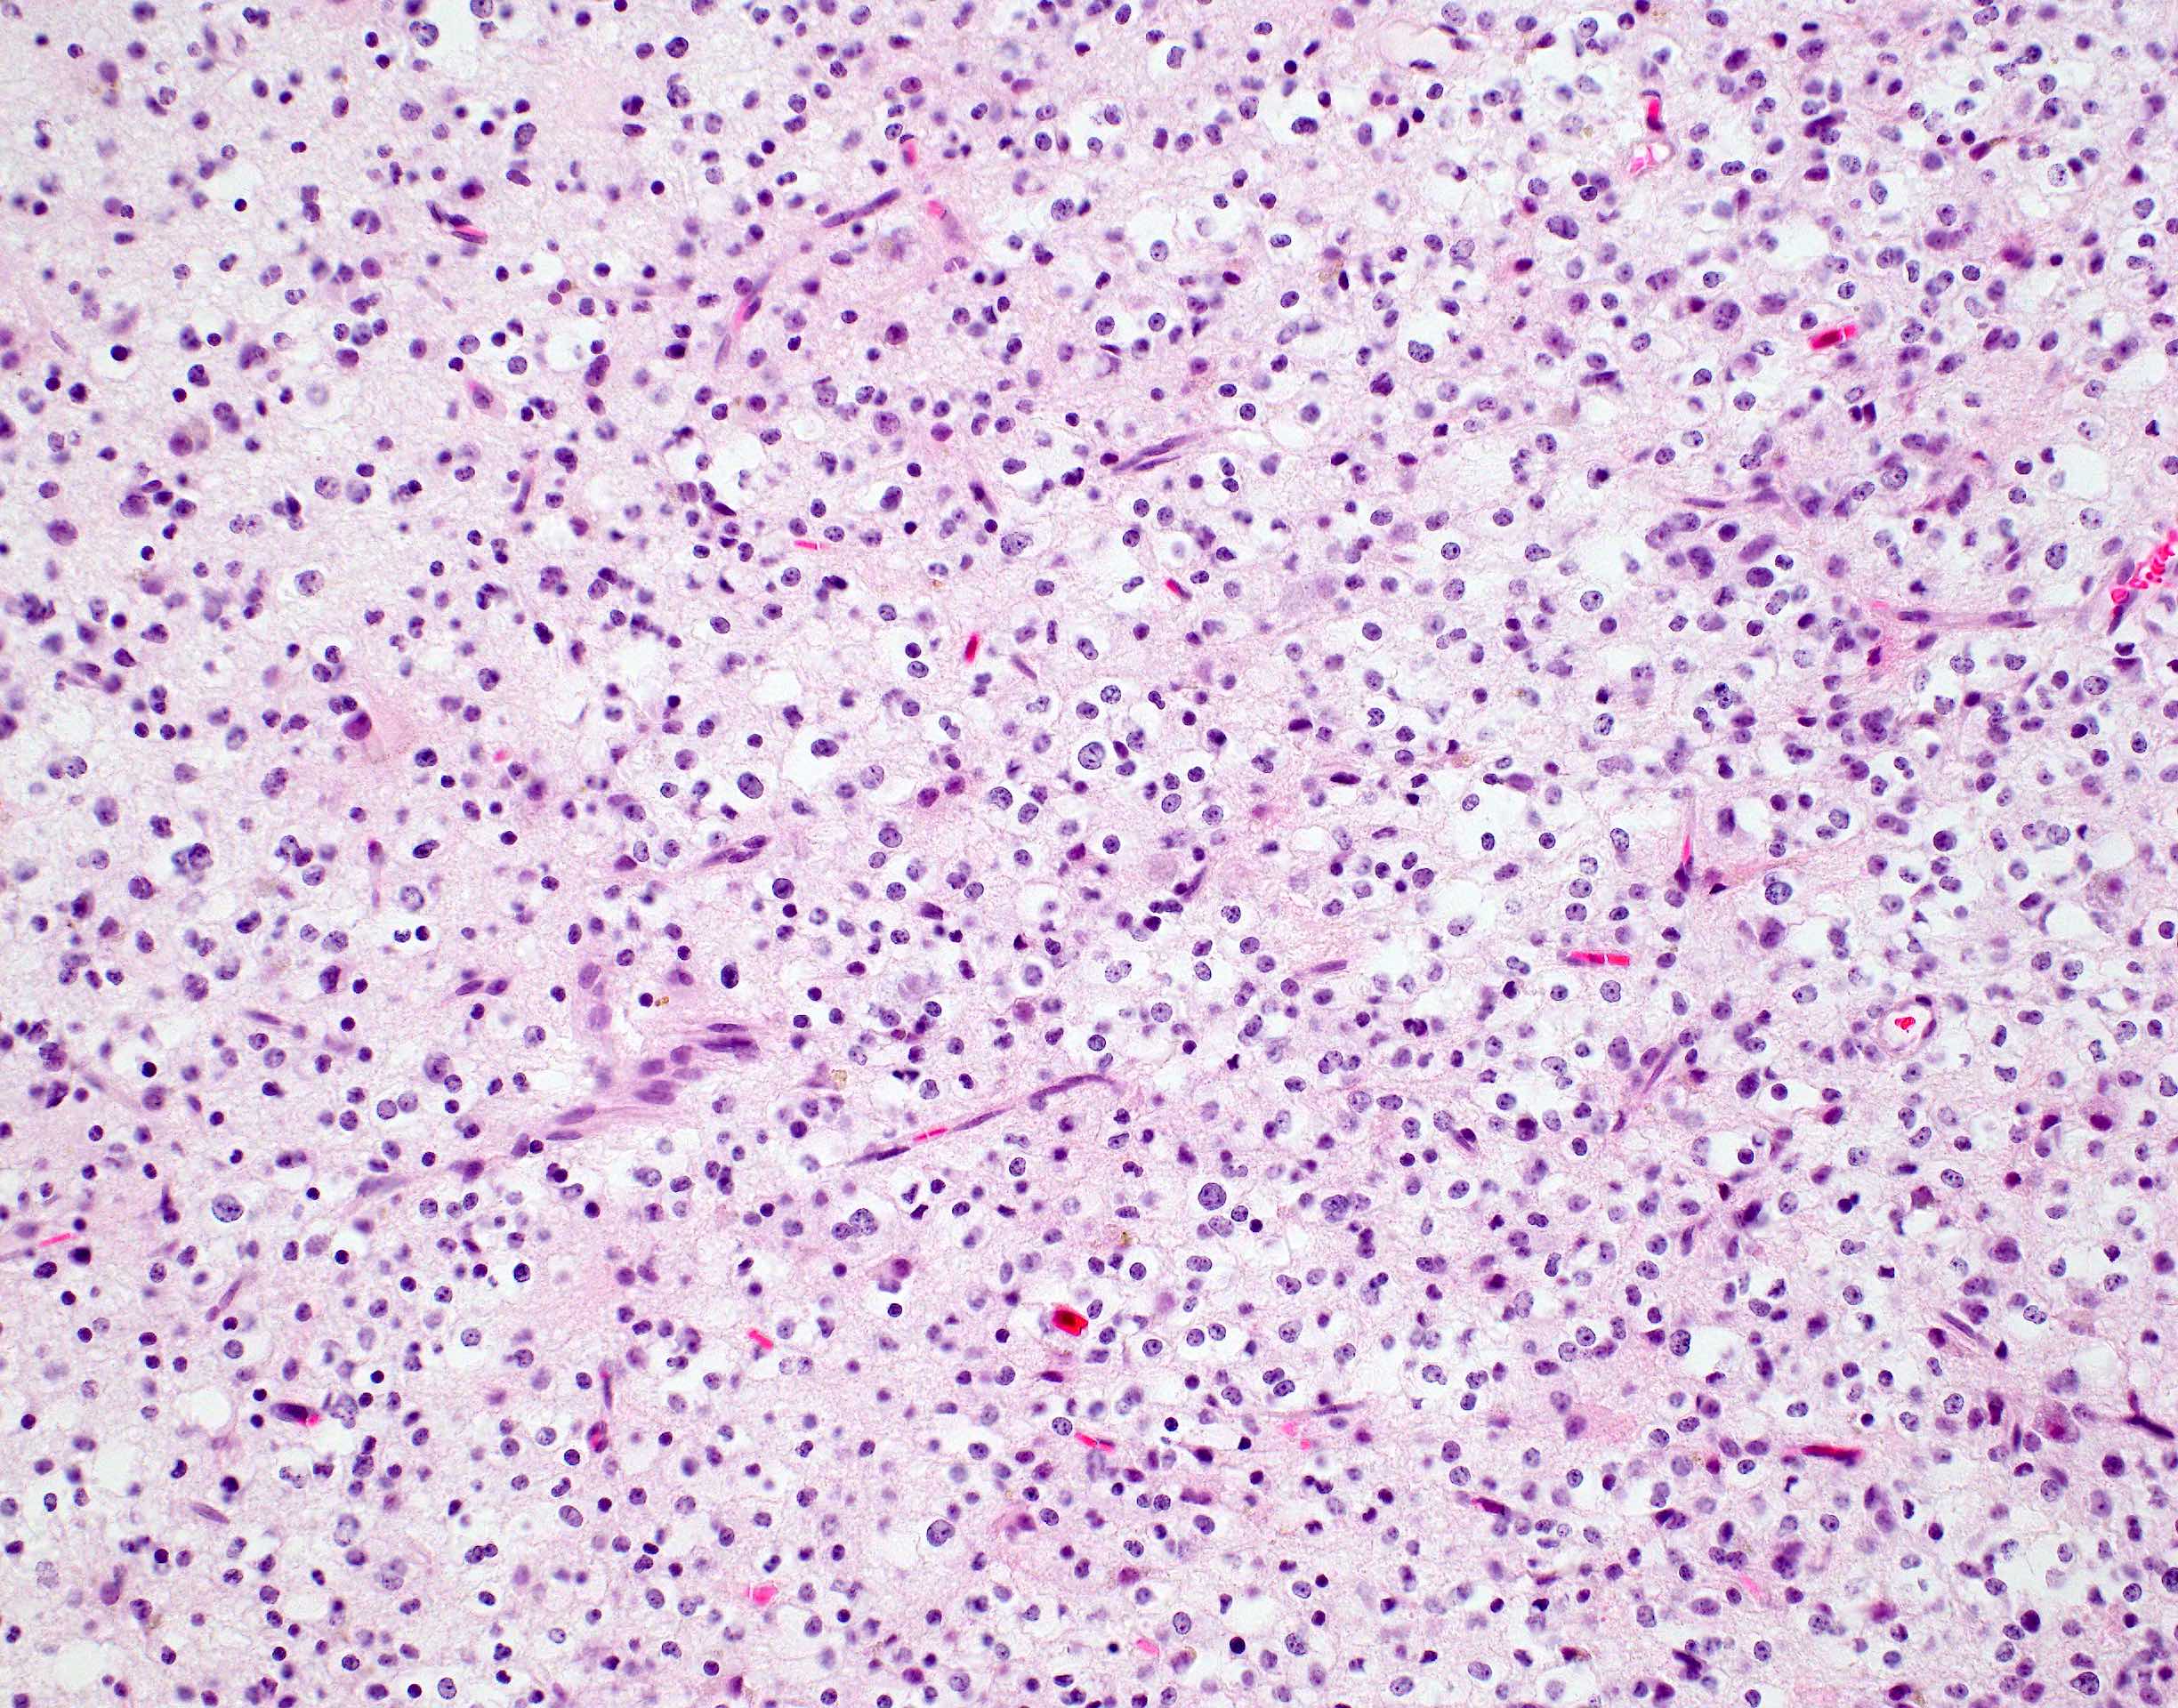

Microscopic (histologic) description

- Closely packed cells with small, round, monotonous nuclei (slightly larger than a normal oligodendrocyte)

- Perinuclear clearing (fried egg appearance)

- Formalin fixation artifact

- Will not be seen on frozen sections or smear preparations

- Network of thin walled, branching blood vessels (chicken wire vasculature)

- Microcalcifications (calcospherites) are characteristic

- Presence of perineural, perivascular or subpial aggregates of tumor cells (secondary structures of Scherer)

- Occasional mitoses and moderate nuclear atypia are still consistent with grade 2 designation (J Neuropathol Exp Neurol 2001;60:248)

- Not uncommon to find well differentiated / fibrillary astrocytic morphology (Acta Neuropathol 1984;64:265)

Microscopic (histologic) images

Contributed by Jared T. Ahrendsen, M.D., Ph.D. and John DeWitt, M.D., Ph.D.